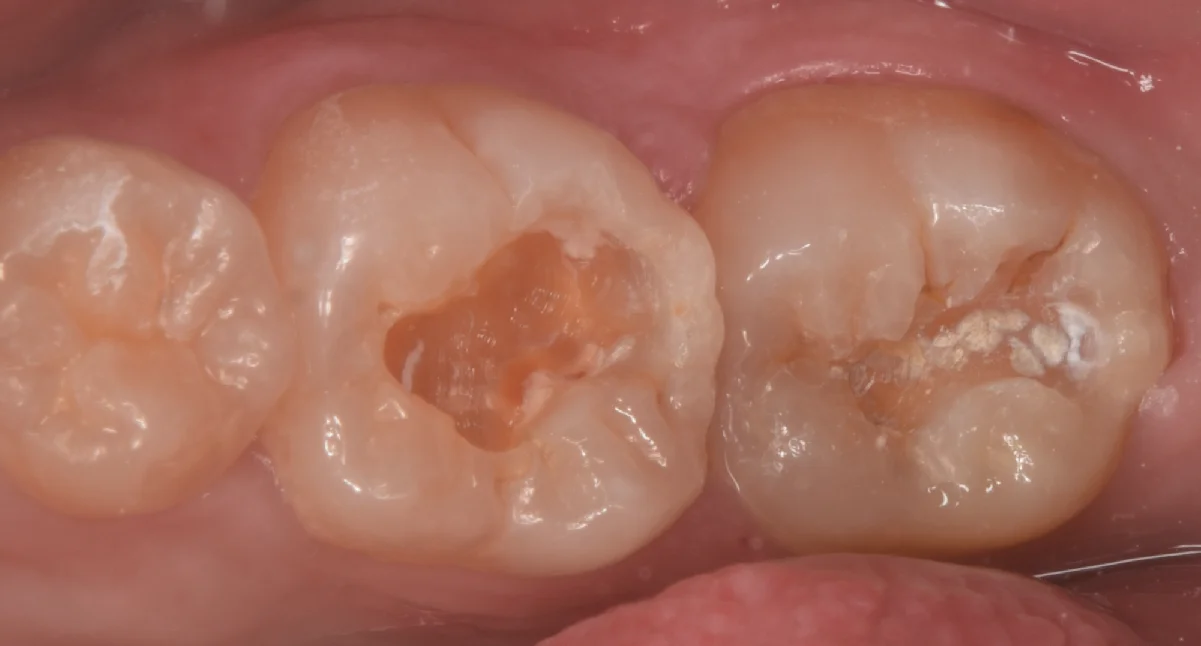

まずは術前からです。

画面中央の白い詰め物の部分と右側の白い詰め物の部分が今回治療する部位になります。

数年前に治療をしたとのことですが、材料が相当に劣化していますね。

古い詰め物だけ除去して虫歯が見えやすい状態にしたのがこちらになります。

真ん中にある歯が実は相当な虫歯のサイズでした。

色は黒っぽくないので虫歯っぽさがないですが、じつはこんな感じで色が薄い虫歯が進行速度が早く、重症化しやすい上に見た目だとわかりづらいので歯科医師としては結構嫌な虫歯のタイプになります。

右側の歯も同様にそこまで深くないように見えます。